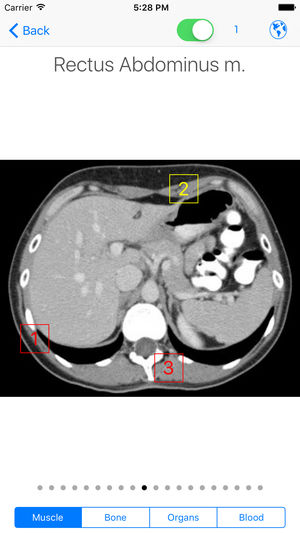

‎WINNER: NLM "Show Off Your Apps" iAnatomy: A simple, portable anatomy atlas of the face, neck, chest, abdomen, and pelvis. -75 images with 60 actual CT scans of the chest, abdomen, and pelvis -Cadaveric images of the face and neck -Separate male and female pelvis -Over 1300 anatomy identifying labe…